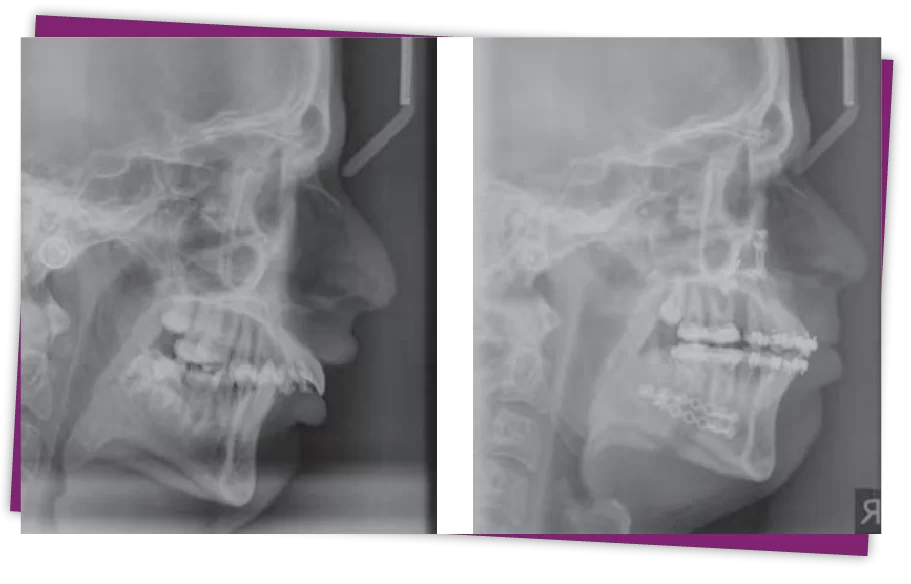

Bước 2: Tiến hành chụp CT scan từ đó xác định nguyên nhân, đánh giá và đề ra các phương pháp điều trị phù hợp nhất cho khách hàng

Để xác định chính xác tình trạng hàm hô, các bác sĩ sẽ tiến hành chụp phim CT 3D toàn hàm, kết hợp với các thao tác chuyên sâu để nắm rõ tỷ lệ hô, từ những thông số có được, bác sĩ sẽ đưa ra phương pháp điều chỉnh hàm hô phù hợp.

Trong trường hợp hàm hô do cung xương hàm trên, bạn sẽ được điều trị thông qua phương pháp phẫu thuật cắt bỏ, điều chỉnh xương hàm, kết quả điều chỉnh hàm hô tại Kubet Thẩm mỹ Worldwide sẽ mang đến cho bạn sự yên tâm và hài lòng nhờ vào những lý do sau: